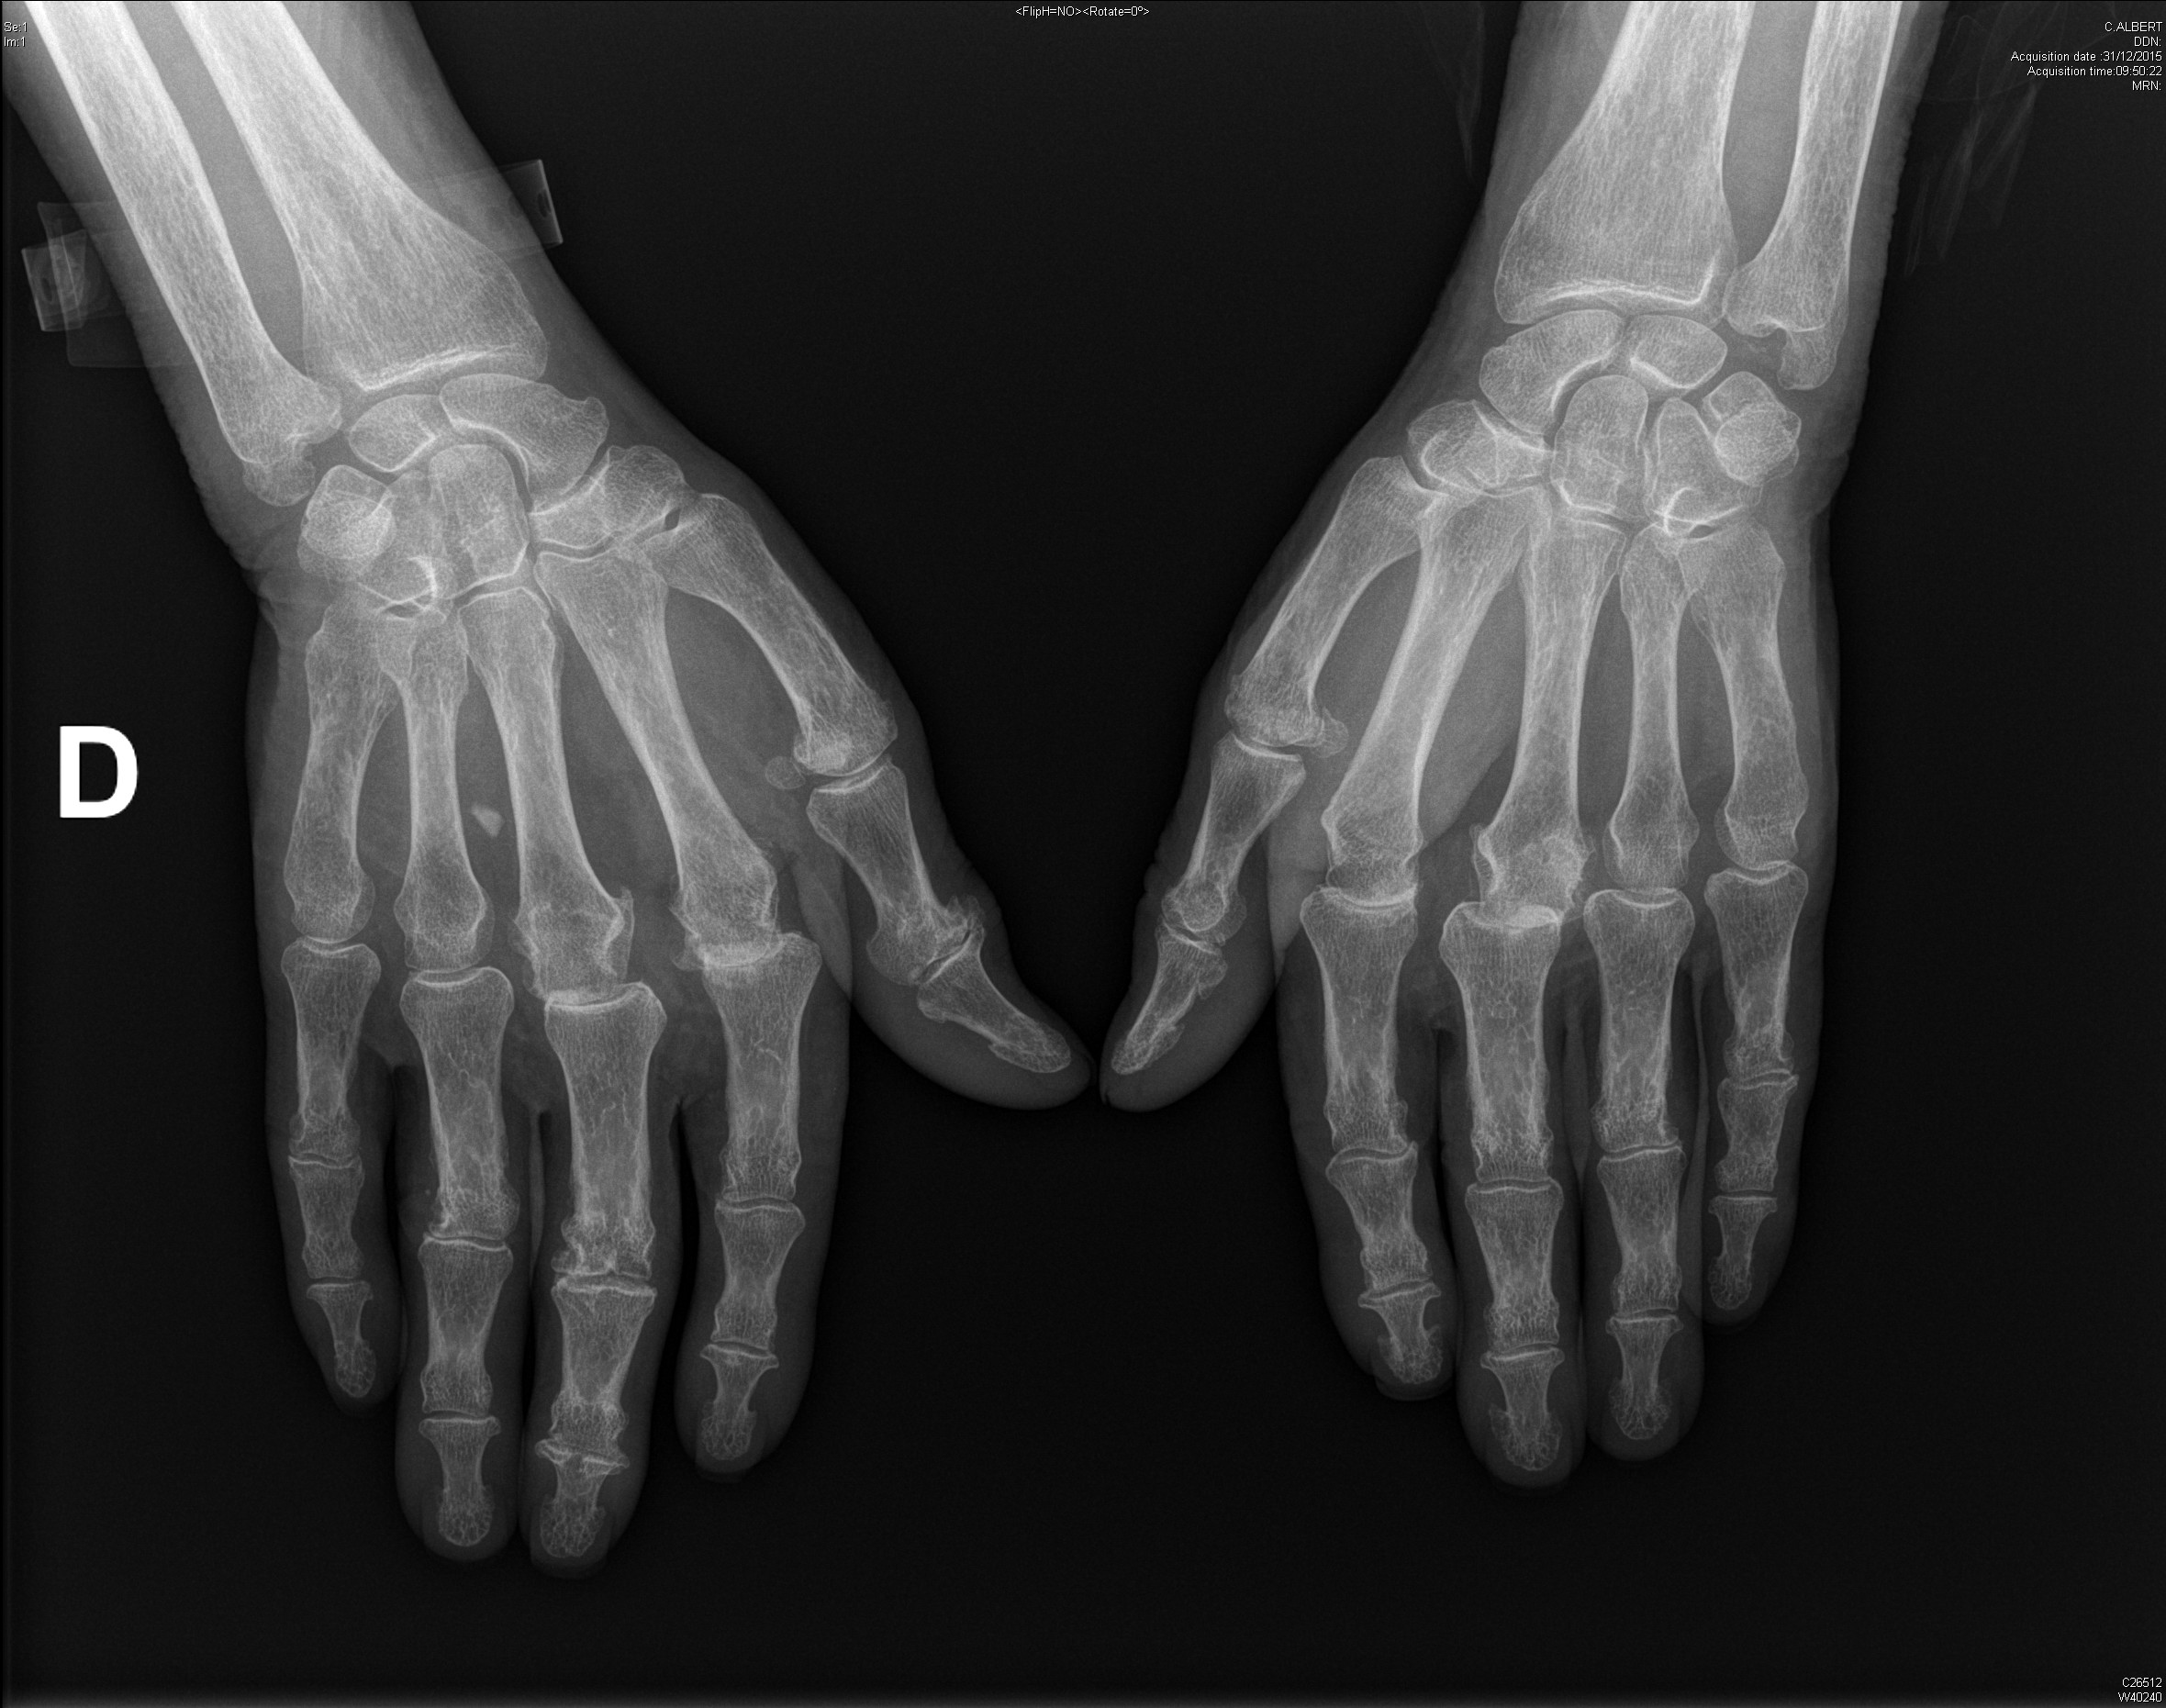

Carpite bilatérale évoluée dans le cadre d'une polyarthrite rhumatoïde

Polyarthrite rhumatoïde débutante, d'emblée érosive

polyarthrite rhumatoïde érosive avec signe de Freiberg radiographique au poignet